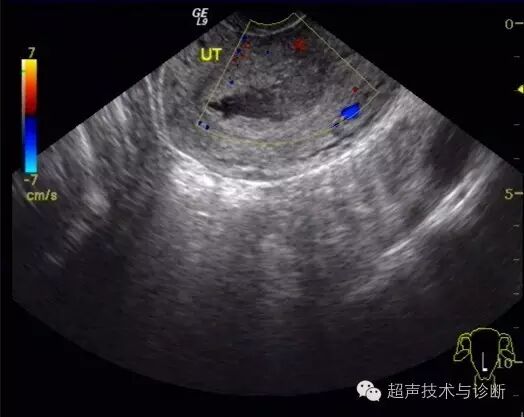

4、超声检查如下(2016。02。01):子宫形态大小正常,宫腔内见一不规则囊性结构,大小4x2cm,透声差,未见双环征及胚芽结构,CDfi未见血流。双侧卵巢可见,右侧附件区可见一囊性结构,大小3x2cm,其内可见胚芽及心管博动。

盆腔扫查见1.4cm积液。

入院血HCG及超声检查图像如下;